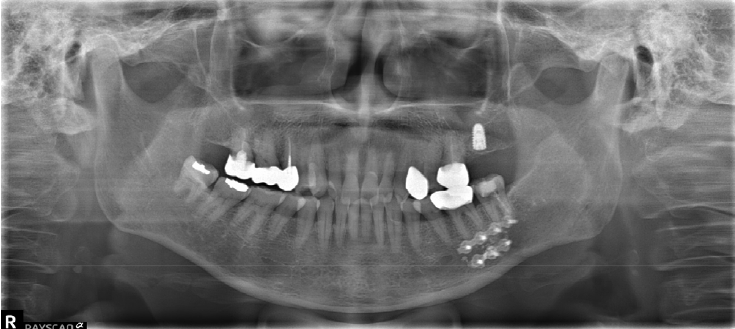

A 41-year-old female reported persistent numbness in the right lower lip and chin following endodontic treatment of the mandibular right second molar (#47). A panoramic radiograph and CBCT revealed extrusion of Calcipex II into the IAN (Fig. 3). She declined surgical intervention and was treated conservatively with mecobalamin and gabapentin. Serial follow-ups at one and three months showed no clinical improvement.

Figure 3.

A. Pre-op panoramic radiograph of Case 2 patient. B. Pre-op CBCT of Case 2 patient.